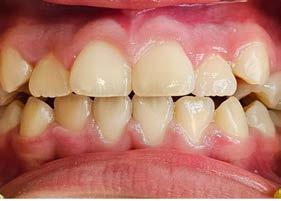

Se observó en la evaluación asimetría facial, tercio inferior aumentado, en la regla de quintos las líneas interpupilares no coinciden con la comisura labial, muestra 2/3 de las coronas superiores al sonreír y perfil retrusivo ocasionado por la distoclusión mandibular (Figura 1).

Su fonación no es clara, ya que presenta congestión nasal y hábito de lengua. Las fotografías intraorales de inicio se muestran en la Figura 2

Sus citas fueron mensuales hasta la obtención de resultados favorables 8 meses después. Consiguiendo cerrar la mordida y obteniendo una línea dental favorable, terminando tratamiento con su aparato removible SN6 en noviembre del 2022 (Figura 4). Se dio de alta temporal, retirando su aparatología funcional.

en julio del 2024, acude la paciente 20 meses después a su cita de control, donde se encontró su línea

media dental estable, así como su mordida anterior manteniendo un overbite favorable, sin presentar indicios de recidiva de mordida abierta anterior, por lo cual se inició su tratamiento en el 2022 (Figura 5).